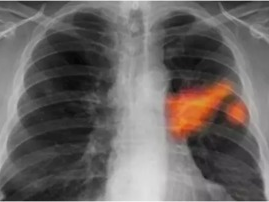

你知道吗?最近有个话题在朋友圈里炒得火热,那就是肺结节的形成可能与油烟有关。是不是觉得有点不可思议?别急,让我带你一探究竟,揭开这个神秘的面纱。油烟,那个看不见的“隐形杀手”想象厨房里弥漫着各种美食的香气,而你正忙碌地烹饪着。这时,你是否注意到,锅里升腾的油烟在空气中飘荡?这些看似无害的油烟,其实可能隐藏着巨...